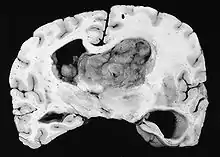

Astrocitoma subependimario de células gigantes

El astrocitoma subependimario de células gigantes o astrocitoma gigantocelular subependimario (en inglés subependymal giant cell astrocytoma, abr. SEGA o SGCA) es un tumor cerebral con un pronóstico favorable, que surge en las dos primeras décadas de la vida y que a menudo, aunque no siempre, se asocia a la esclerosis tuberosa. Según la clasificación de la OMS de los tumores del sistema nervioso central, este tumor benigno se clasifica en el Grado I.[1]

Generalmente, el SEGA se muestra como una lesión nodular bien circunscrita en relación con la masa cerebral adyacente. En la literatura son muy raros los casos de propagación (por ejemplo, a la médula espinal) y de malignización.[2] Este tumor es claramente visible en la resonancia magnética, donde presenta realce tras la aplicación del medio de contraste.

Los astrocitomas subependimarios de células gigantes se dan sobre todo en niños y adultos jóvenes. Dado que el tumor se desarrolla preferentemente en las paredes del sistema ventricular en la proximidad del foramen de Monro, el flujo de salida del líquido cefalorraquídeo suele verse alterado a medida que el tumor crece. El tumor suele crecer muy lentamente y se muestra en las imágenes de RM y TC como una masa circunscrita con calcificaciones y signos de sangrado antiguo. En algunos casos, el SEGA es la manifestación inicial de la esclerosis tuberosa y, por lo tanto, es un criterio diagnóstico importante. Sin embargo, sólo entre el 5 y el 20% de todos los pacientes con esclerosis tuberosa desarrollan SEGA.[3]

Histológicamente, son características de la lesión las células gigantes astrocíticas; sin embargo, la morfología de las células tumorales puede variar desde células poligonales con citoplasma vítreo y núcleos ganglioides hasta células fusiformes en una matriz fibrilar. Las células tumorales muestran una expresión variable de GFAP, S-100, sinaptofisina y neurofilamentos.